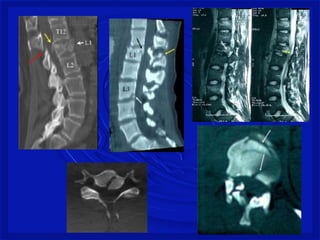

As lesões ocorrempor: -Flexão, extensão, rotação, compressão por impacto axial ou combinação desses mecanismos. Mecanismo de Trauma Raqui- Medular com fratura

FRATURA COM LUXAÇÃOCOMPLETA – TORÁCICA BAIXA

Gravidade do trauma •DEPENDE SE A MEDULA É ATINGIDA • Lesão medularcervical é a mais comum– 2/3 • C4 a C7 – mais vulnerável a lesão • Torácica - proteção de costelas • Toracolombar– T11, T12 e L1 • Lesão estável ou instável • Difícil de avaliarno pré hospitalar. • Considerartoda lesão instável até se prove o contrario